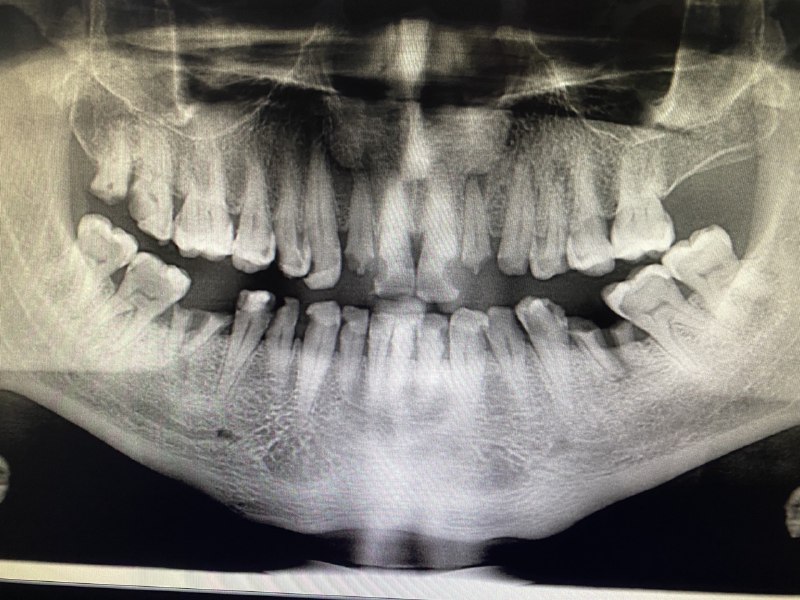

During intra oral examination we found he has a ,multiple cavities in all teeth

We start our treatment plan by Control phase:

1.Extraction of hopeless teeth.

2.Periodontal therapy .

Then we improve the periodontal health

the patient diagnosed by generalized mild chronic gingivitis and moderate periodontitis grade B So we did an scaling ,Then we gave the patient oral hygiene instructions brushing and flossing use a mouth wash and a proper diet